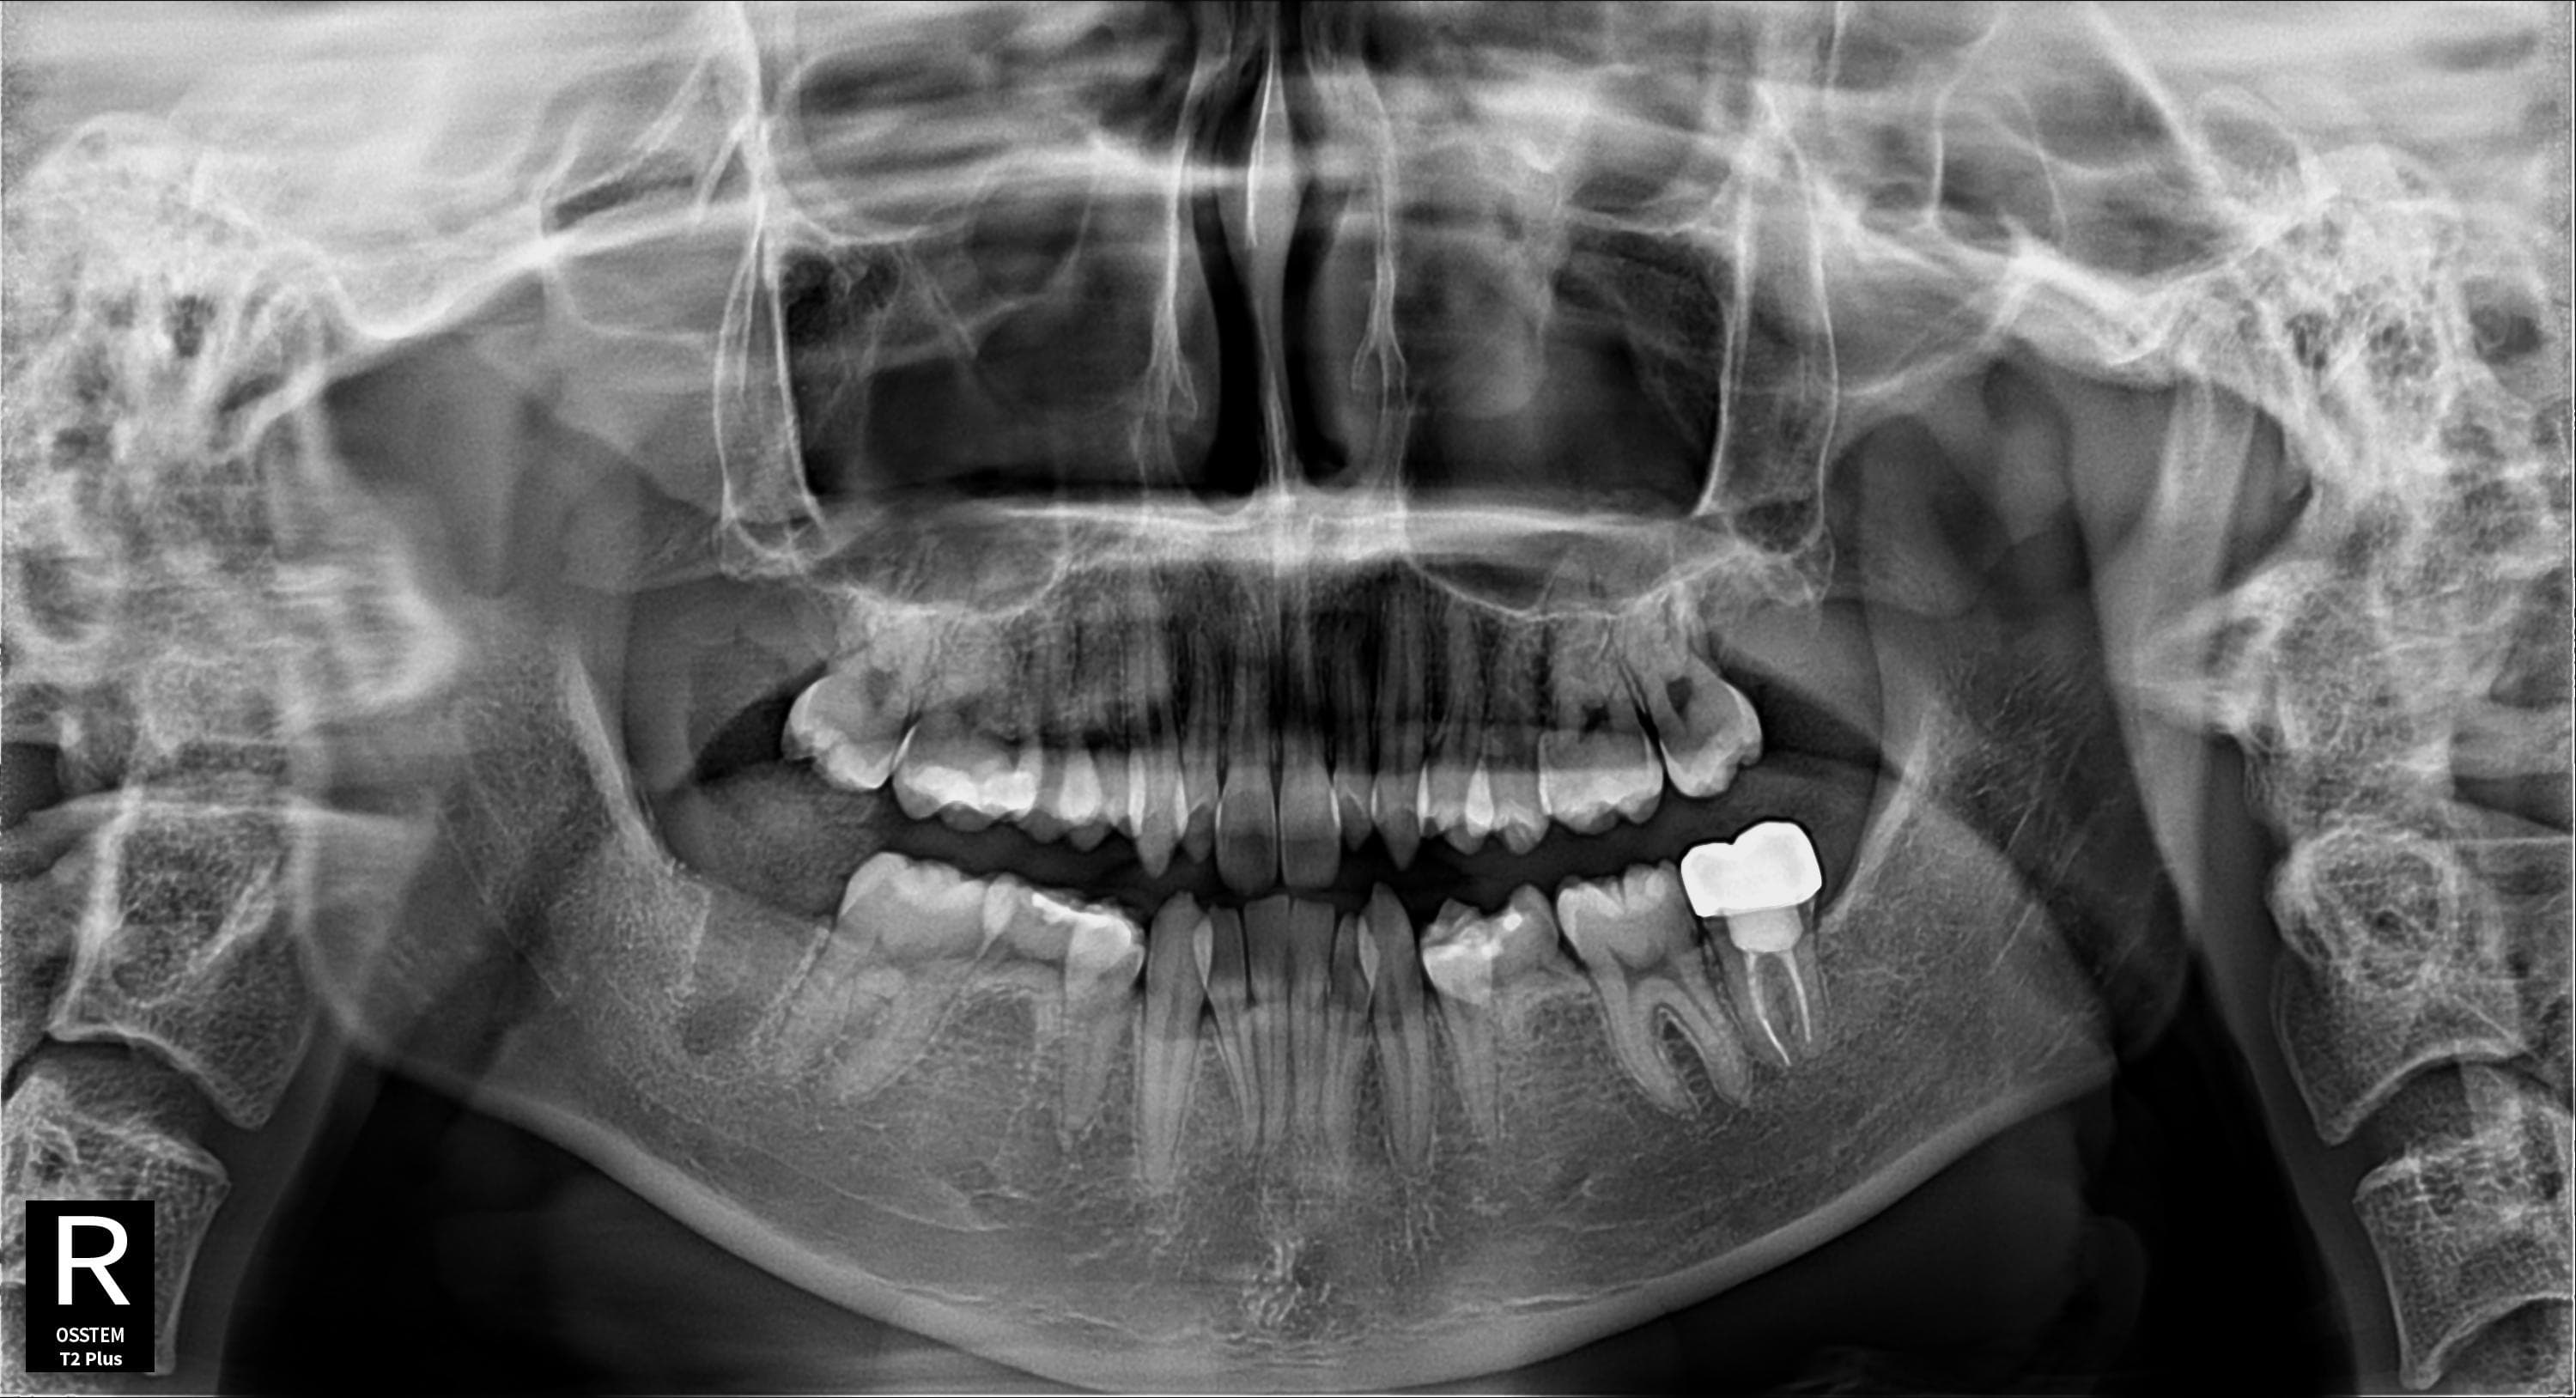

우측 아래 사랑니 발치

우측 아래 사랑니 발치 후 깔끔한 회복

Before

After

우측 아래 사랑니 발치 후 잇몸 깔끔하게 회복